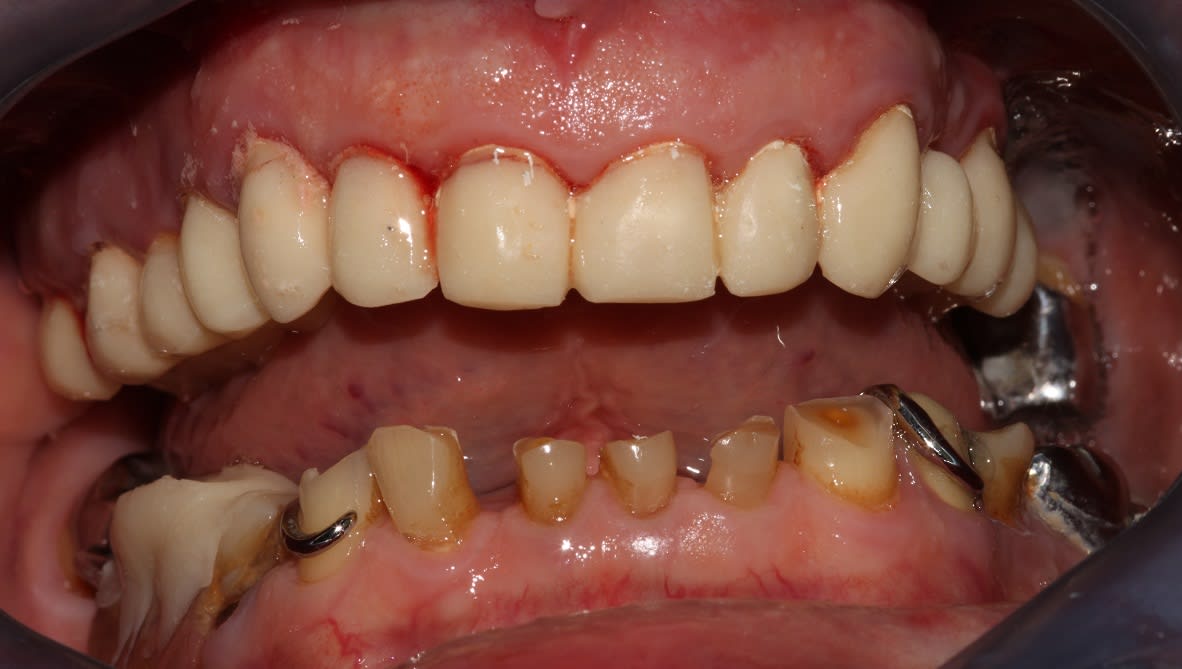

Le provisoire du haut à été réalisé ce matin en bloc technique, un peu plus de 3 h.

Et putain, une photo en occ serrée, là on voit rien bougre d'âne!

(Au deuxième tour, je relèverai un peu la courbe de Spee sect 1. Au départ je pensais également rentrer un peu 24 25, mais en fait je pense que ça devrait s'équilibrer avec le bas, je vois en fin de semaine. Et le milieu est un peu décentré, mais au bout de 3h j'en avais marre)

Tu pouvais remonter 2mm de plus, facile, non ?

La DV? Si c'est ça je préfère le faire au second tour, ça me laisse plus de laxité, et sur ce genre de cas j'ai tendance à régler le haut comme un complet, donc là on est à la bonne longueur.

je suis pas d'accord sur la longueur des dents maxillaire, mais passons

j'aime pas la forme de 24/25/26, ça me rappelle le dernier cas que j'ai présenté, ou 14/15 faisait verrou)

(pour la morpho secteur 2, les cuspides vest mériteraient effectivement un bon coup de rabot, mais j'attends de voir une fois remontées les antagonistes. Et 36 terminera sur le plateau, la mésiale est bouffée infra osseuse)

Sur les photos c'est coton, le patient l'aide pas, il fait une grimace et un sourire pas franc ensuite.

Je suppose que tu as réglé avec un truc genre faite "fe, ve"

A mon avis si le gars est satisfait de ses futures dents il va plus découvrir et sourire, à surveiller avec les prov.